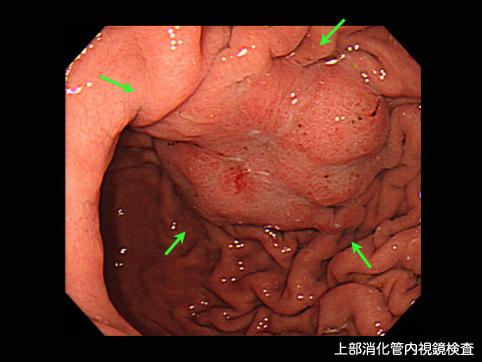

Criteria of Hist.ClassificationMalignant epithelial tumor/Adenocarcinoma

LocationStomach/Angle

Technique, MethodEndoscopy

Macroscopic TypesType 1 Protuberant (polypoed) type/

Size35 - 40

Depth of Tumor Invasionsubserosa (subadventitia)